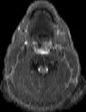

Visible Human male: Sectio transversalis 1227

CT

NMR

Pd T1 T2